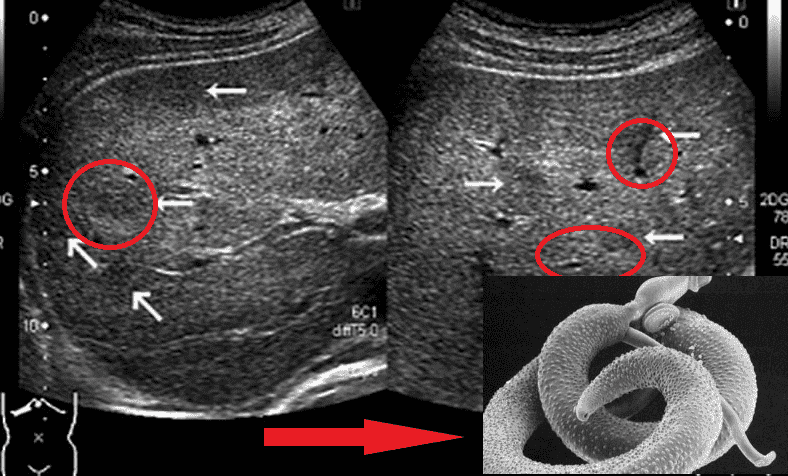

Εκπρόσωποι των ελμινθίων που προσβάλλουν ζωτικά όργανα είναι οι Taenia solium, Echinococcus (Echinococcus granulosus), Trichinella (Trichinella spiralis). Ο Echinococcus είναι το προνυμφικό στάδιο του ελμινθίου του γένους Echinococcus. Υπάρχουν πολλά είδη παρασίτων.

Εκατομμύρια αποικίες παρασίτων κατακλύζουν ολόκληρο το σώμα και διεισδύουν στην καρδιά, στους πνεύμονες, στα νεφρά, στο ήπαρ, ακόμη και στον εγκέφαλο!

Ένας εγκέφαλος που έχει προσβληθεί από τα παράσιτα